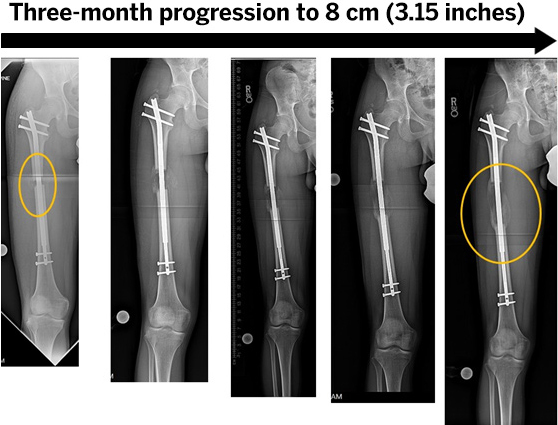

Limb Lengthening